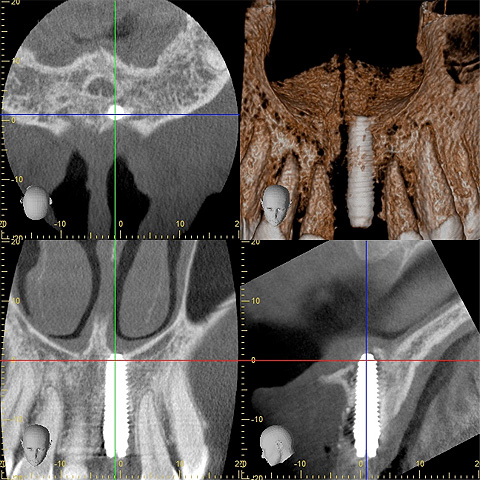

CT写真でも、理想的な位置に新しいインプラントが入ったことが確認できます。

オペから2ヶ月後の口腔内写真。

綺麗に歯茎も治りました。

レントゲンも撮影して、インプラントと型取り用パーツがしっかり嵌合しているか確認します。

CTによる断層図です。

インプラントが斜めに入っていることがわかります。

噛み締めが強い方の場合は、斜めに埋め込まれたインプラントだとトラブルが起きてしまうことがあります。

咬合力に対して垂直に力を受け止めることができる位置に、インプラントを埋め直す必要があります。

インプラント埋入後のCT写真です。

長いサイズのインプラントを硬い鼻腔底の骨に噛み込ませることで、即日で仮歯を入れることができます。